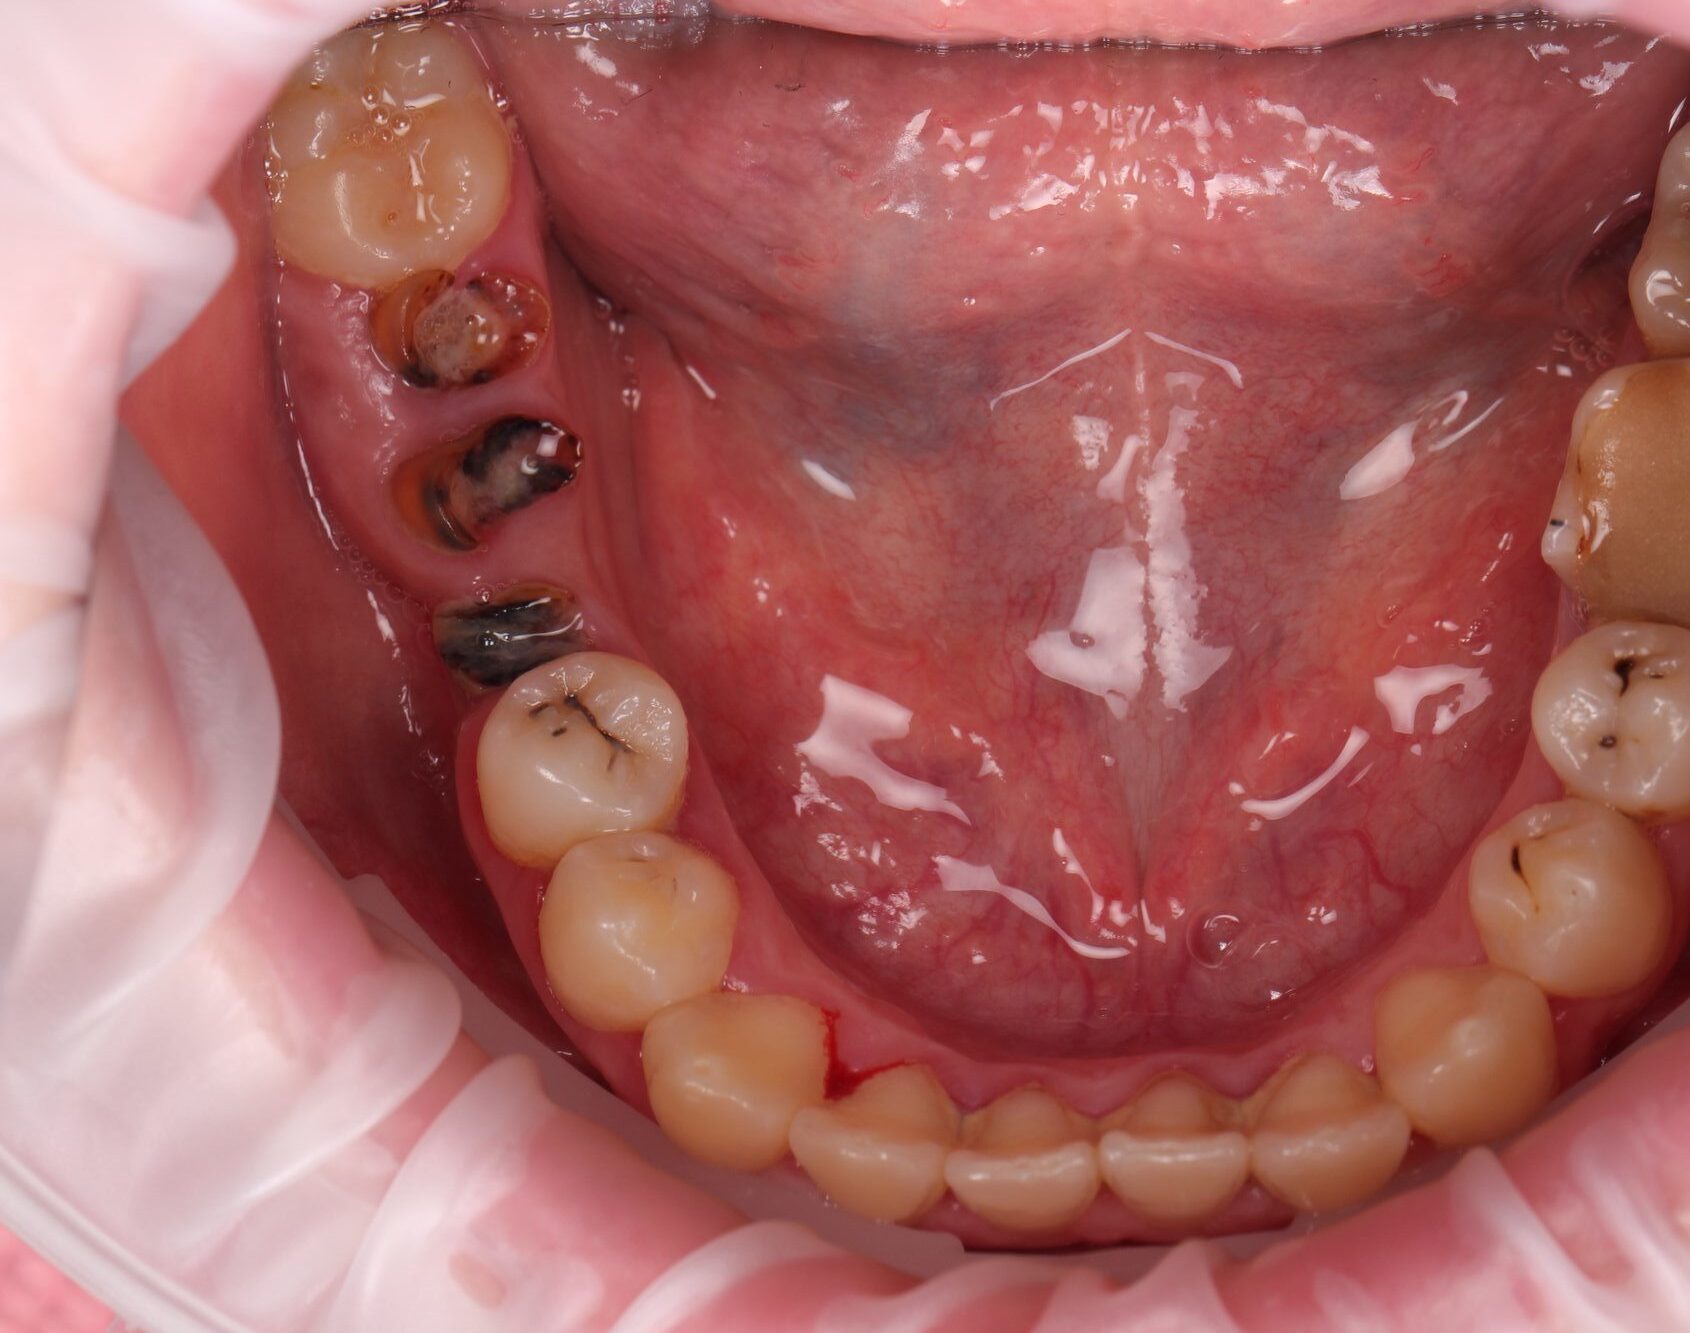

Інна, 24 роки

До

після

Тривалість лікування:

1,5 рік

проведено:

• Професійна Гігієна

• Терапія

• Реставрація

• Лікування кореневих каналів

• Видалення зубів

• Брекет-система

• Імплантація

• Протезування

• Видалення зубів мудрості